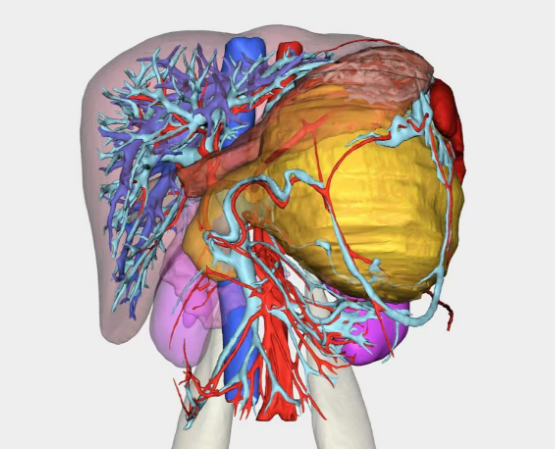

田毅峰教授、陈实教授通过术前充分的评估和规划,利用三维成像和数字分析,智能推演出行胰头切除联合主胰管十二指肠重建的可能性,在术中利用荧光超声导航定位保护胆管,精确切除肿瘤,利用高清放大技术重建2mm胰管,行胰管十二指肠“Takada”吻合,术后恢复良好,实现了真正意义上保留脏器和生理功能的微创。经查阅文献,微创下胰管十二指肠“Takada”吻合在世界范围内尚未见报道。

田毅峰教授、陈实教授经过数字成像智能评估后,准确分析并制定出微创下切除肿瘤的最便捷路径,为赵某实施机器人辅助胰体尾脾切除术,术中借助机器人高清的三维视野、灵活的机械臂、精细操作,在狭小的空间中最终完整切除肿瘤,成功实现微创手术,术后恢复良好,患者腹部只留下4cm的隐匿伤口,做到“大切除、小伤口”,充分体现了机器人智能系统在胰腺外科中的极致优势。

数字成像智能评估手术路径